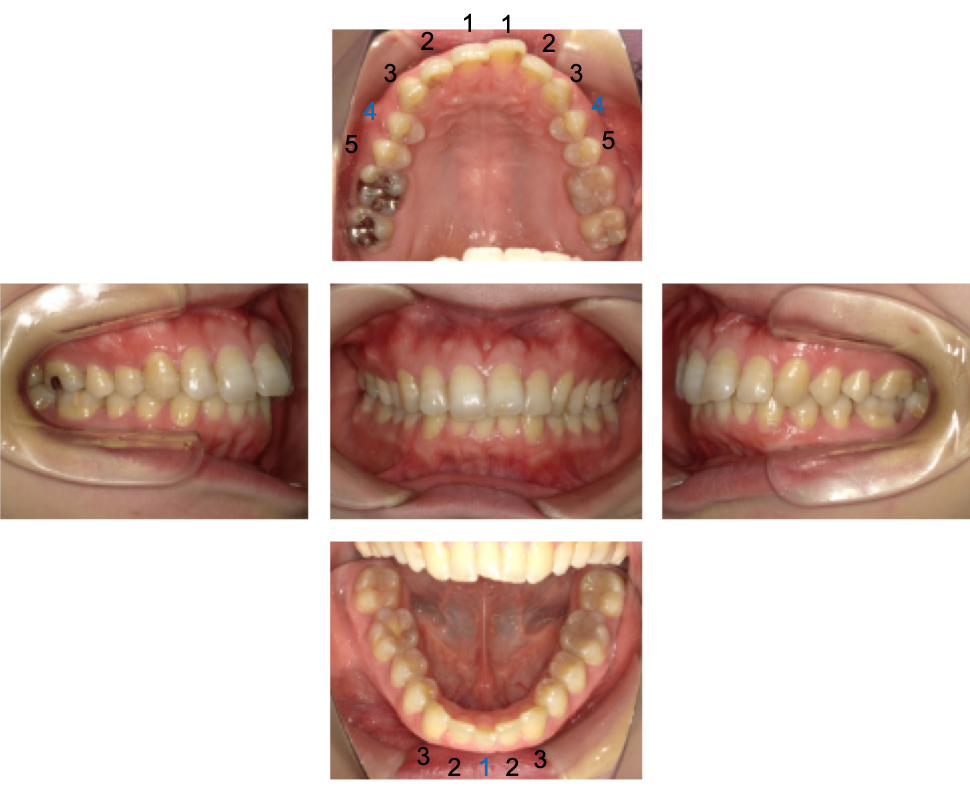

下顎は、生まれつき下の前歯が1本欠如している「スリーインサイザー(3 incisor)」の状態でした。下の歯が1本無いことがわかります。

※青色の番号…抜歯箇所です(上顎左右4番 下顎左1番)

左右4番の歯を抜いたあと、3番の歯をうしろへ動かしました。

その結果、3番の歯は5番の歯のすぐ隣まで移動し、2番と3番の歯の間にすき間ができています。口ゴボを改善するため左右1番2番を後ろへ下げました。

下顎前歯3本(2番・1番・2番)のうち、真ん中の1番の歯を抜歯しました。そのため、下顎は(3番・2番・2番・3番)という並びになっています。